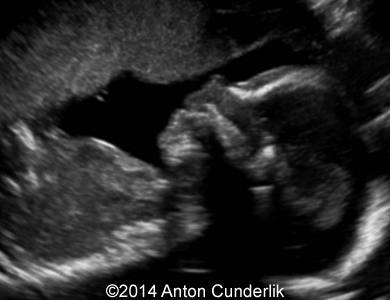

Image 2, 3, 4, 5, 6, 7: 30 weeks of gestation; the images show cystic structure within the fetal tongue that later turned out to be thyroglossal cyst.